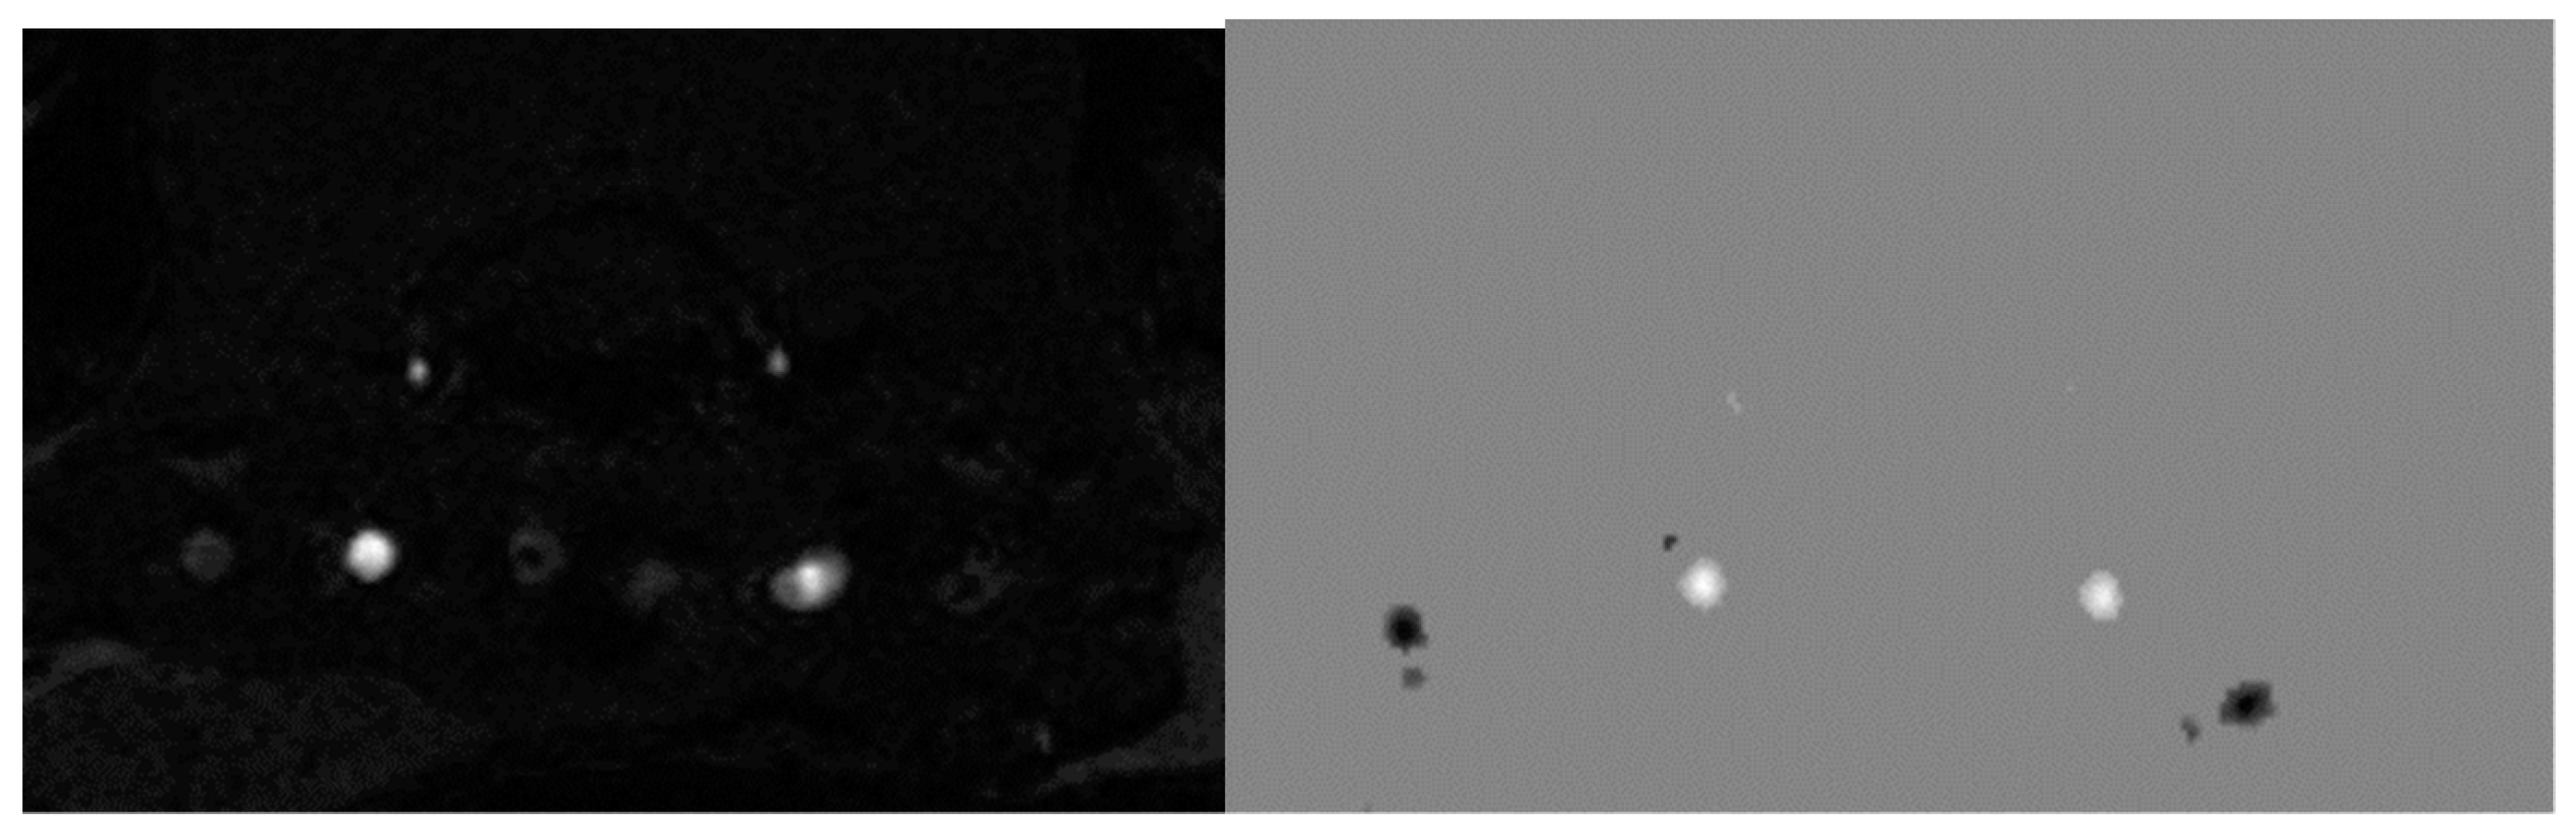

4.6. Magnetic Resonance Spectroscopy (MRS)

We performed the analysis of rat dorsal hippocampus neurometabolites following the execution of the abovementioned methods [57].

Voxels were manually placed according to a structural T2-weighted MRI image. All proton spectra were recorded by spatially localized single-voxel stimulated echo acquisition mode (STEAM) spectroscopy, with the following pulse sequence parameters: TE = 3 ms, TR = 5 s, and 120 accumulations. Uniformity of the magnetic field was tuned within the selected voxel using FastMap before each spectroscopic recording. The water signal was inhibited with a variable pulse power and optimized relaxation delays (VAPOR) sequence. The experimental 1H magnetic resonance spectra were processed, and the quantitative composition of metabolites was determined with a custom-made program similar to that of the LC Model software package [59,60]. The baseline correction was conducted automatically by the program to determine the spectral baseline for fitting the spectrum obtained by 1H MRS. The process of fitting was presented on the real-time plot, and the fitted data were stored in numerical form.

The facilities of the program allow the following 12 brain metabolites to be fitted to the MRS spectrum: N-acetylaspartate (NAA); phosphorylethanolamine (PEA); choline compounds (Cho); creatine + phosphocreatine (Cr + PCr); myo-inositol (mIno, Ins); alanine (Ala); lactate (Lac); glutamate + glutamine (Glu + Gln); aspartate (Ast); γ-aminobutyric acid (GABA); glycine (Gly); and taurine (Tau). The percentage ratios of metabolites were analyzed (Supplemental Table S1). Please see Figure 17 for corresponding images.

Figure 17. The regions of the MRS spectrum registration in three orthogonal planes of the brain of studied rats.